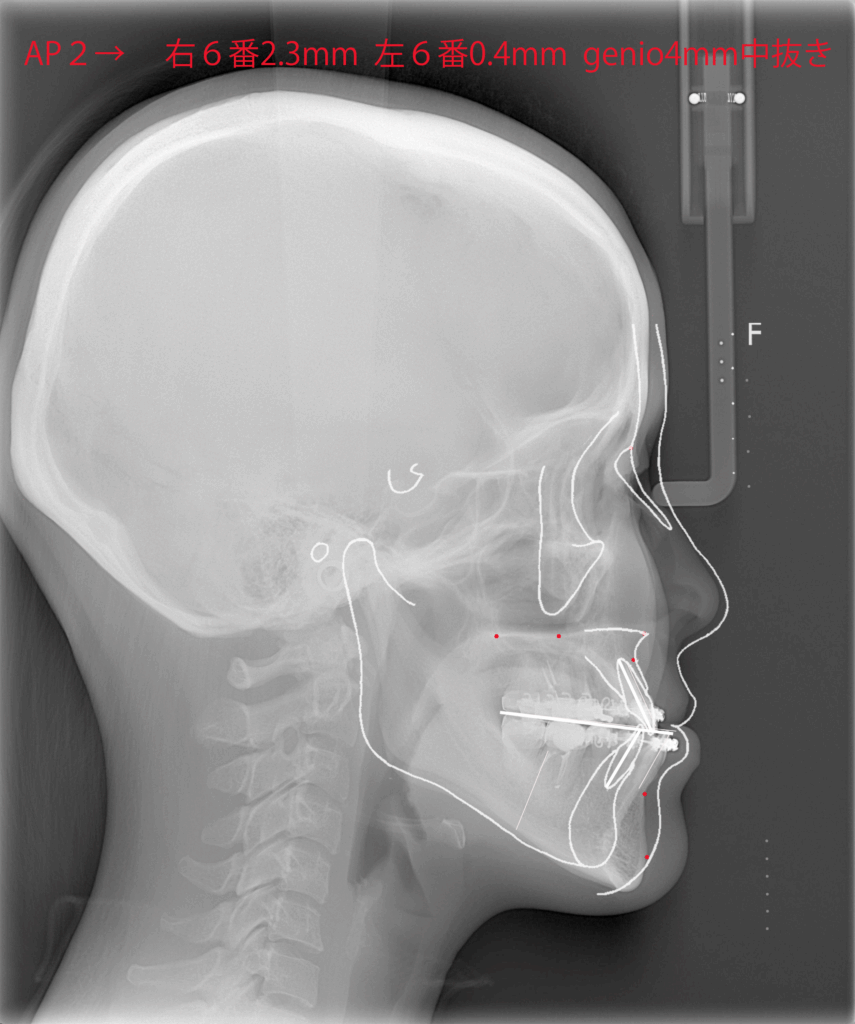

レントゲンを用いて骨格の特徴を把握します。白線の輪郭は標準的な骨格を表しています。標準骨格と比べると、下顎が前に出ていて、なおかつ垂直方向に長いことがわかりました。

白線の標準骨格に一致するように骨の移動量を決めていきます。上顎は鼻下で2mm前進し、臼歯部で2mmほど上方に移動させます。全体として上下顎は時計回転することになります。顎先は4mmの中抜き短縮です。